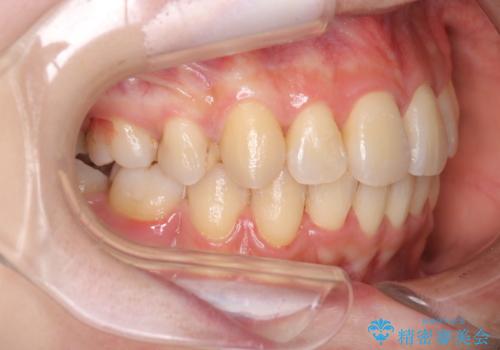

ガタガタの抜歯矯正を裏側ワイヤーを使っての目立たない矯正

- ハーフリンガル

- 八重歯とガタガタを主訴に来院されました。

目立たないワイヤー矯正を希望されたので、上下左右のはを1本ずつ抜歯して、ハーフリンガル(上顎だけ裏側)にて矯正をすることにしました。